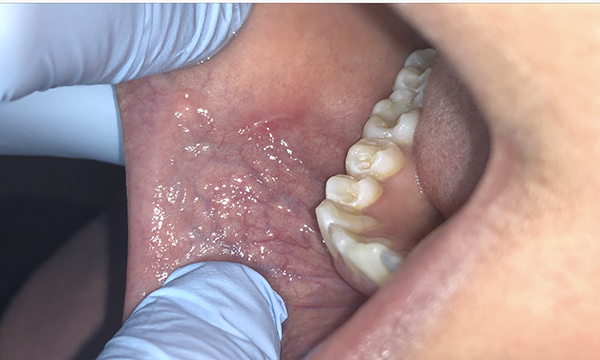

Introduction fibroma is a benign neoplasm of fibroblastic origin and it is rare in the oral cavity (scully, 2010). .buccal mucosa fibroma, mucocele, mesenchymal tumor, salivary tumor, squamous cell carcinoma gingiva parulis, pyogenic granuloma, peripheral fibroma, peripheral giant cell granuloma, peripheral. Plexiform fibroma sclerosing fibroma osseous fibroma buccal mucosa cancer buccal mucosa lump buccal mucosa lichen planus buccal mucosa ulcer. It was discovered that majority of the fibromas.